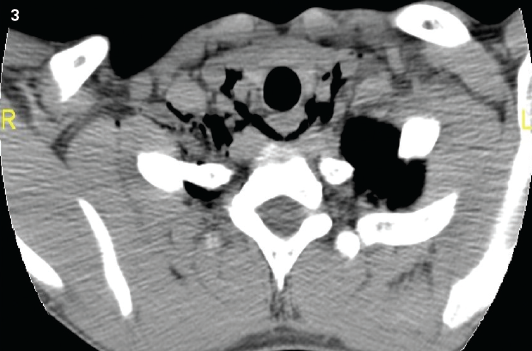

Radiographs (Figures 1 and 2) and computed tomography (CT) scans of the chest and neck were ordered (Figures 3 and 4) and confirmed pneumomediastinum but failed to identify an etiology. Because spontaneous pneumomediastinum is uncommon, the patient was admitted to the pediatric floor for further workup and evaluation. Otolaryngology was consulted.

Figure 3. A chest CT scan revealed the presence of air in the paratracheal region.